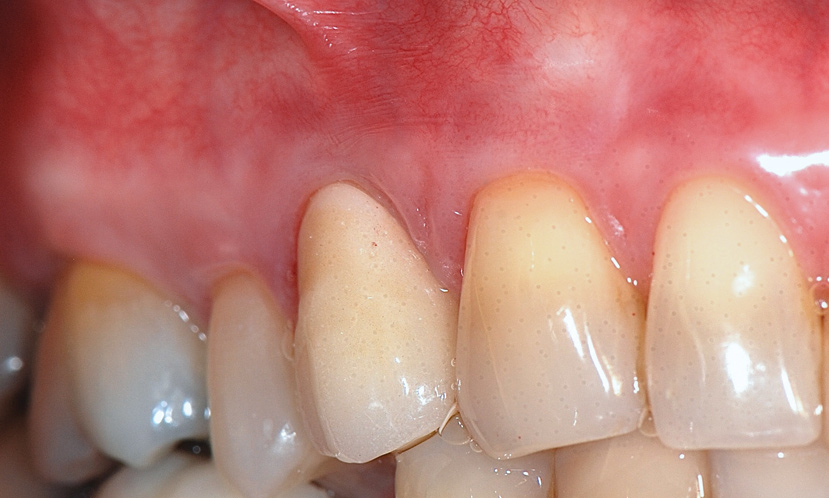

The workshop's group on periodontal soft-tissue root coverage procedures evaluated the predictability of root coverage procedures for single- and multiple-tooth Miller Class I and II10 periodontal recession defects. The workshop concluded that predictable root coverage was possible for Miller Class I and II recession involving a single tooth. When compared with the use of acellular dermal matrix graft (ADMG) (donor tissue) or EMD (porcine origin), procedures using a subepithelial connective tissue graft (SCTG) harvested from the patient's palate provided the best root coverage outcomes in conjunction with a coronally advanced flap.11 As alternatives to autogenous donor tissue, the workshop found strong evidence to support the use of an ADMG or EMD in conjunction with a coronally advanced flap and limited evidence to support the use of platelet-derived growth factor and xenogeneic collagen matrix.11 In addition, root coverage procedures were found to be effective for Miller Class I and II recession defects affecting multiple teeth, although the evidence is limited.11 Figure 1 and Figure 2 show the pretreatment and 1-year postoperative views of a soft-tissue root coverage treatment with SCTG and EMD that used a coronally advanced flap and a tunneling procedure. Figure 3 and Figure 4 depict the pretreatment and 3-year postoperative views of a root coverage procedure with ADMG and EMD that used a coronally advanced flap and a tunneling procedure (this patient was noncompliant following surgery and did not return to the office until the 3-year postoperative appointment).

(1.) Pretreatment view of single incisor with gingival recession exposing the root.

Figure 1

(2.) Postoperative view after one year following treatment with SCTG (harvested from palate) and EMD using a coronally advanced flap and a tunneling procedure.

Figure 2